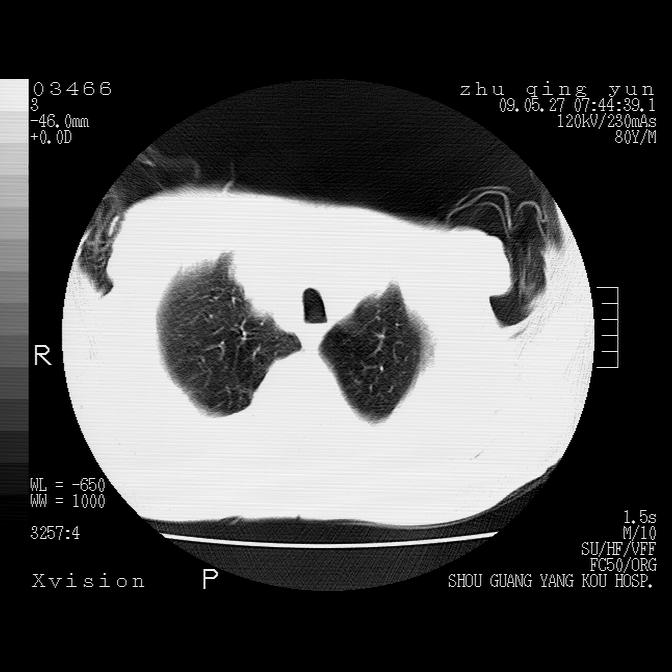

病人男性,年龄80,气喘来院,其他病史不太详细,1月前有过恶心,呕吐,在当地人民医院做过钡餐,诊断胃炎,

1)考虑左肺中央型肺癌并阻塞性肺炎,后下纵隔受侵伴纵隔淋巴结转移。2)双侧少量胸腔积液,胸膜增厚。3)心包积液。

左肺下叶见多发片状及结节状病灶,左肺基底段支气管闭塞,纵隔内见多发淋巴结肿大,纵隔向左侧移位,左侧胸廓变小。应该是左肺下叶中心型肺癌,纵隔淋巴结转移,左侧肺内转移,左肺基底段肺不张,阻塞性肺炎。

1)考虑左肺中央型肺癌并左肺下叶阻塞性肺炎、不张;左胸膜腔积液、心包积液、纵隔淋巴结转移;癌肿累及左心房。2)左心室大。冠状动脉壁钙化斑。